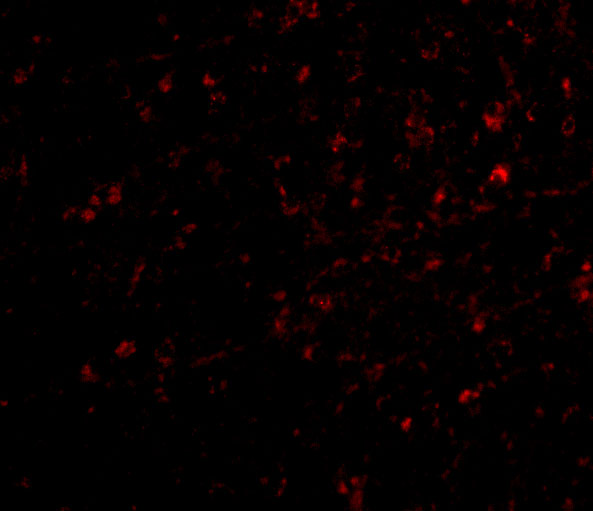

- Immunofluorescence (IF)